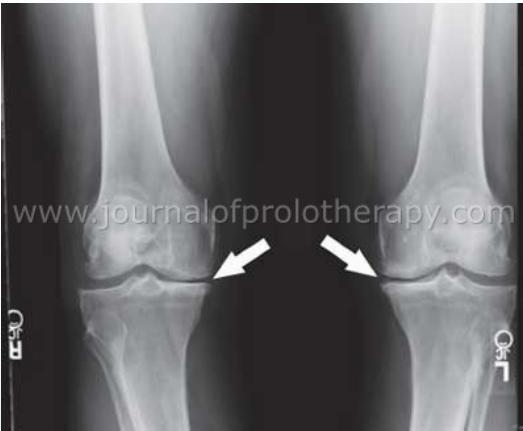

- AP standing

- Stress films (for ligament assessment)